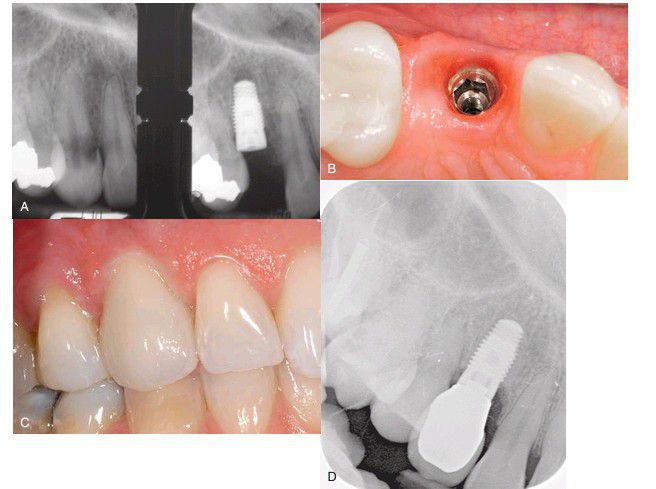

Single tooth replacement

. (A) Radiograph showing nonrestorable tooth before extraction (left) and after (right) extraction with implant in place. (B) Implant after the uncovering and healing period and ready for restoration. (C) Final result. (D) Final radiograph.